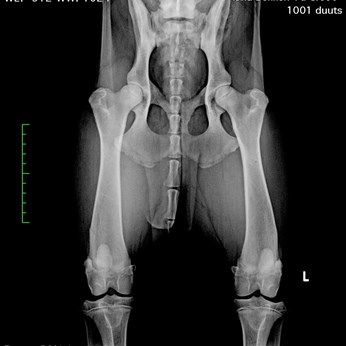

Name: Andrea von Haus Ka und Mi (Duuts)

Gender: Female

Date of birth: 28-06-2017